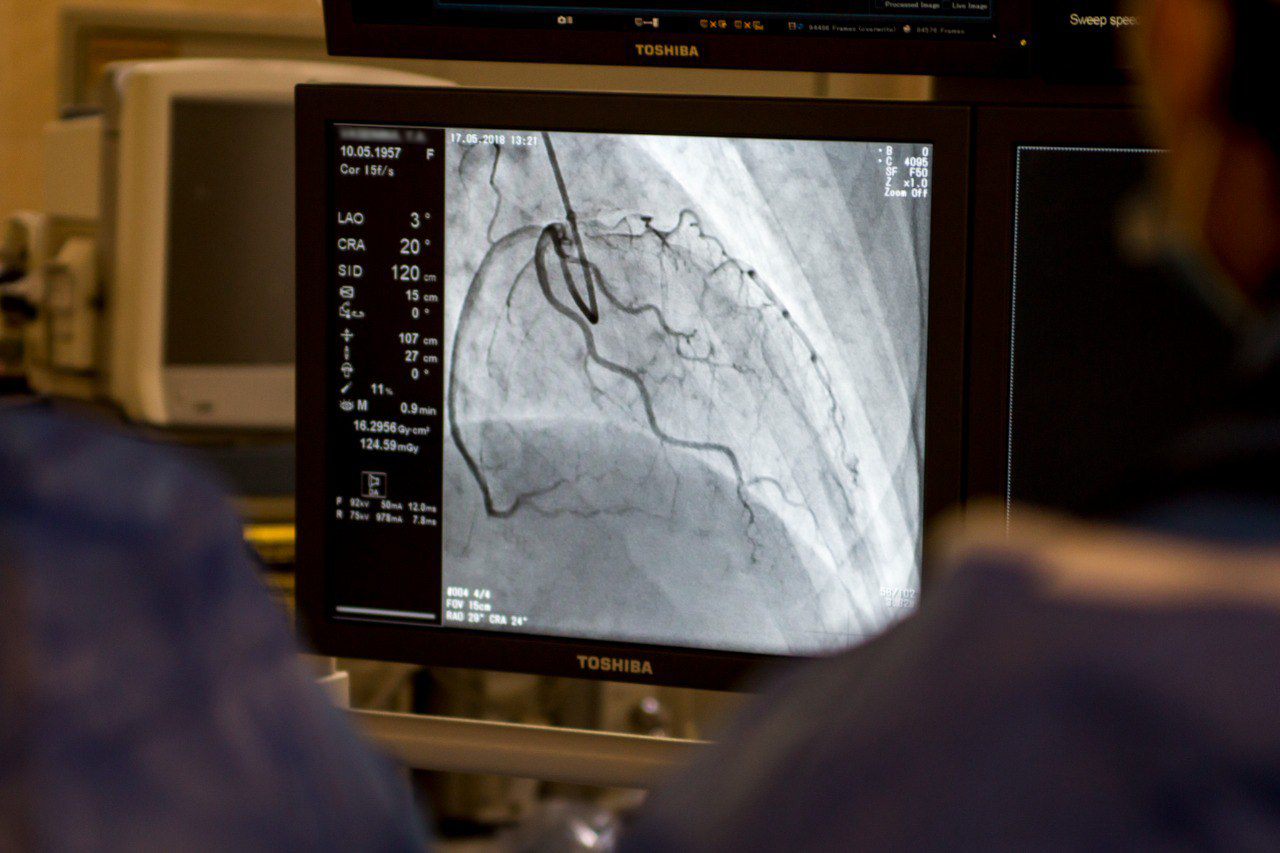

Нашу специальность — рентгенэндоваскулярные методы диагностики и лечения — для краткости называют рентгенхирургией, а иногда — ангиографией по названию аппарата, который мы используем. «Ангио» — сосуд, «графия» — рисование. Ангиографический комплекс включает в себя операционный стол, прозрачный для рентгеновских лучей, и особый тип рентгеновского аппарата, который генерирует лучи и фиксирует изображение сосудов, структура которых «подсвечивается», когда лучи проходят через контрастное вещество. Вводим контрастное вещество в нужный сосуд с помощью длинного и узкого катетера и видим, что происходит внутри: атеросклеротические бляшки, дефекты, сужения, окклюзию (закрытие сосуда). Очень важное и востребованное исследование — коронарография — мы изучаем состояние коронарных артерий — кровеносных сосудов сердца.

Отделение рентгенхирургических методов диагностики и лечения (РХМДиЛ) в 52-й больнице было создано в 2012 году. На 1-м этаже 5-го корпуса была оборудована операционная, оснащенная ангиографом Toshiba и другим необходимым сопутствующим оборудованием. В начале свой деятельности мы выполняли коронарографии, баллонную ангиопластику и стентирование коронарных сосудов пациентам с острыми инфарктами и стенокардией напряжения. В дальнейшем эндоваскулярное направления в нашей клинике динамично развивалось, увеличивались объемы выполняемых операций. В 2022 году на 3 этаже 5 корпуса была введена в эксплуатацию вторая ангиографическая операционная для плановых пациентов, оснащенная ангиографом Siemens для проведения как коронарных, так и периферических вмешательств. Дополнительное оборудование позволяет нам выполнять внутрисосудистые ультразвуковые исследования (ВСУЗИ), исследование резерва кровотока (ссылка) — фракционного (ФРК) и моментального (МРК), позволяющего определить давление до стеноза и после стеноза, а также криобаллонную и радиочастотную аблацию. Также мы активно используем визуализацию коронарных артериях методом оптической когерентной томографии. Активно применяется в практике и ротационная атерэктомия при сильно кальцинированных поражениях артерий — еще одно современное эндоваскулярное вмешательство. Раньше подобной технической оснащенностью могли похвастаться только ведущие федеральные центры. Сейчас же все технологии и методы, которые есть в мировой рентгенэндоваскулярной диагностике и хирургии, мы можем предложить пациентам нашей клиники.